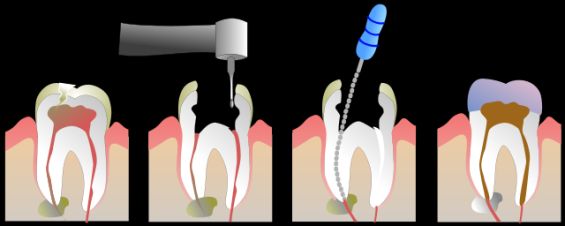

Лечение периодонтита заключается в выявлении и ликвидации очага заболевания. Стоматолог проведет необходимые процедуры, направленные на угнетение патогенной микрофлоры в зонах воспаления. При наличии жидкости в области воспаления специалист обеспечит ее отток и изолирует полость внутри корневых каналов.

Существует несколько способов лечения хронического апикального периодонтита. Если есть такая возможность, то чаще всего прибегают к терапевтическим методам. С их помощью проводится очистка корневых каналов от остатков пломбы и других загрязнений. Затем проводится отвод экссудата и промывка каналов раствором антисептика.